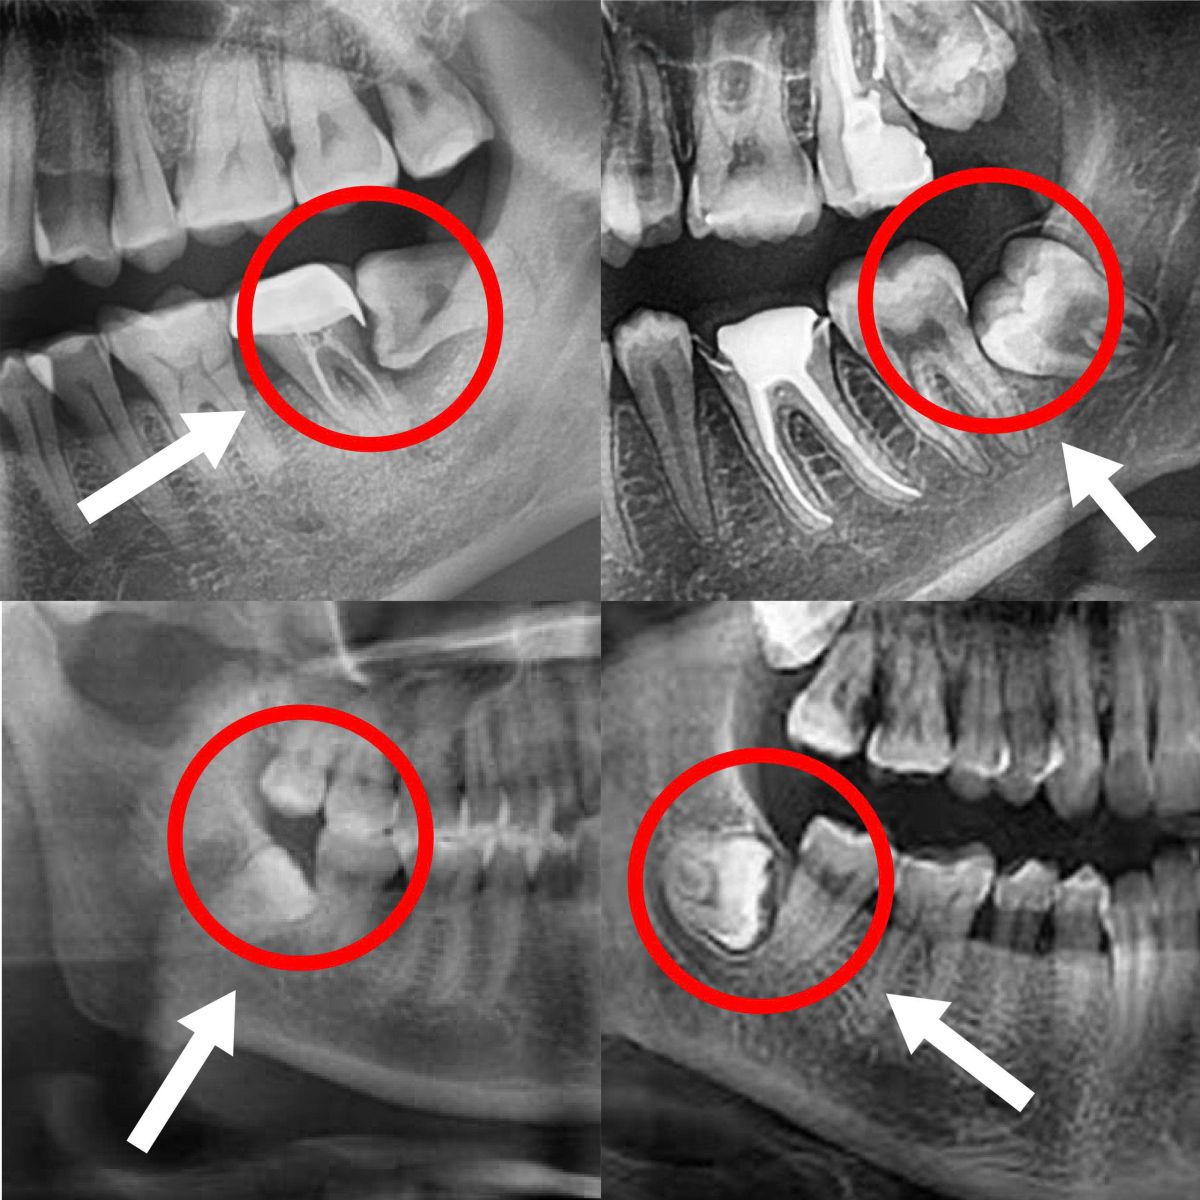

Răng khôn là những chiếc răng mọc sau cùng trên cung hàm, thường xuất hiện khi xương hàm đã phát triển ổn định. Chính vì vậy, răng khôn thường không đủ chỗ để mọc thẳng, dễ mọc lệch, mọc ngầm và gây ra hàng loạt vấn đề răng miệng.

Bước 1: Thăm khám & chụp CT Cone Beam 3D

Đánh giá chi tiết vị trí răng, dây thần kinh, hướng mọc để lên kế hoạch điều trị chính xác.